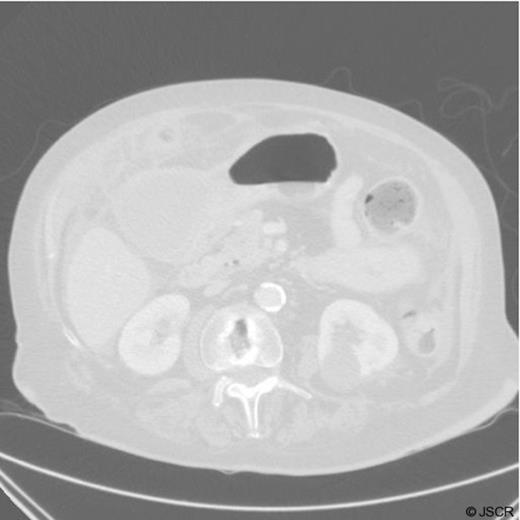

Histological specimen demonstrating the cyst overlying the stomach

Specimen demonstrating a gastric duplication cyst in the gastric lining